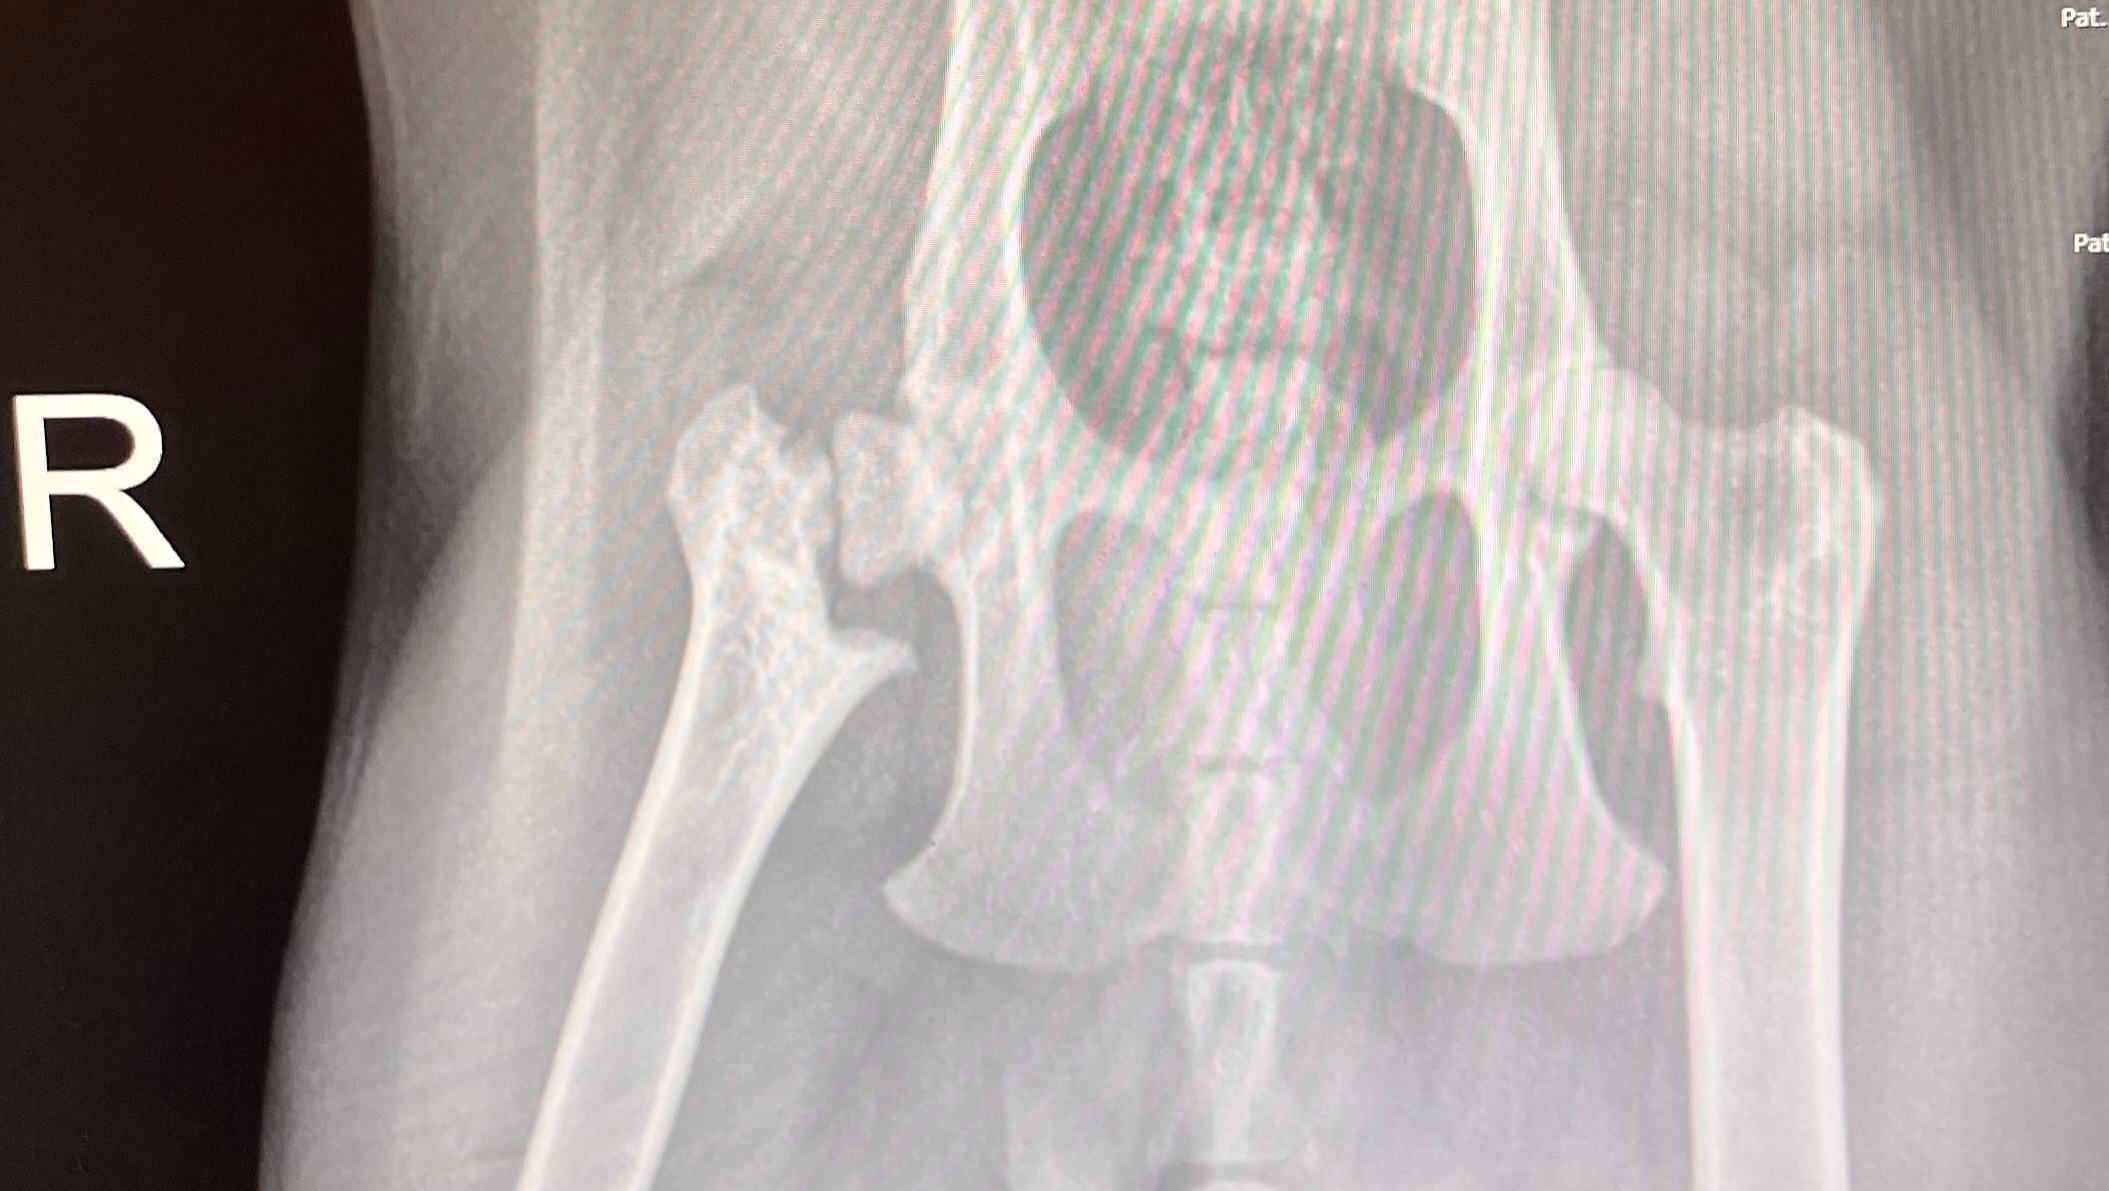

I got Mr. Rogers vaccinated and did blood testing; he came back negative for all tests! Over the next few days, I noticed he was limping, didn’t jump to play with toys, and wasn’t putting pressure on his right hind leg. I made an appointment with my vet and scheduled to get x-rays done. Yesterday, I was able to see the x-rays and couldn’t believe my eyes. His femur had been fractured.

After the vet was able to show a specialist his x-rays, they believed it to be capital femoral physeal dysplasia. He was most likely born with this condition, and he will always have an issue with his right hip. There is a procedure that can be done called FHO (Femoral Head Ostectomy) that will relieve a lot of pain and help Mr. Rogers live as normal a life as possible. This procedure, while less expensive than a complete hip replacement, is still going to be costly. The estimated cost is between $1,000 and $3,000, and I will be getting a more specific cost next week.